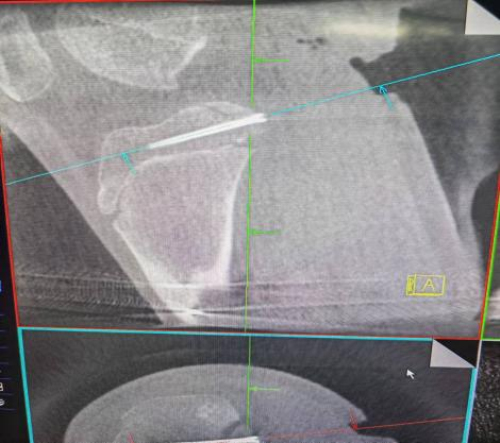

术后X光片